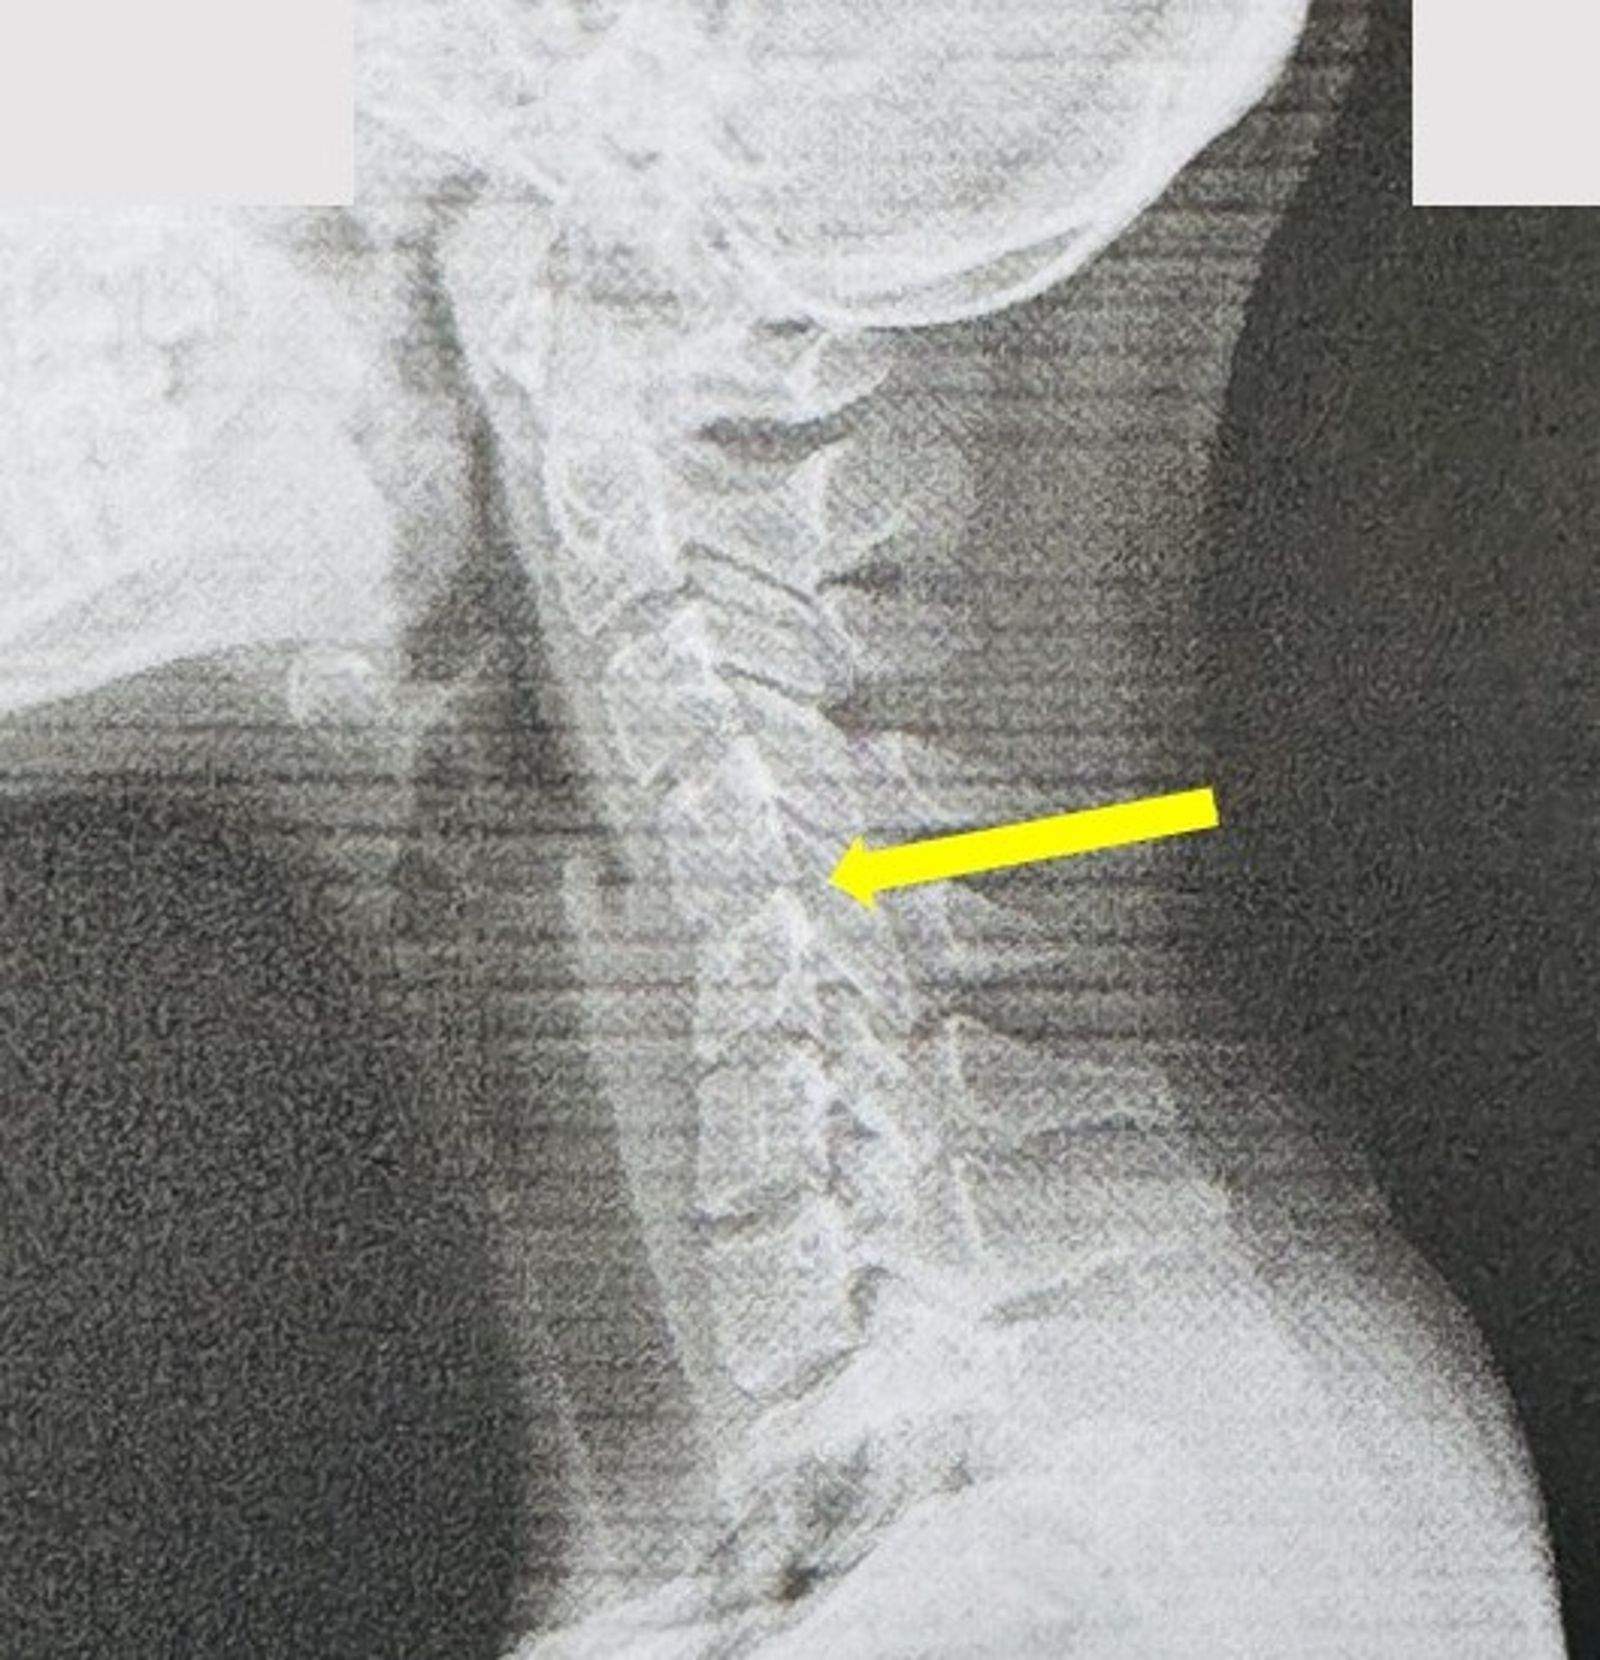

「才20歲,頸椎卻已60歲?」神經內科醫師葉宗勳分享病例,一名20歲女病患脖子僵硬,頭痛不已,一照X光發現竟是「低頭族」最殘酷真相,其頸椎弧度已從優美的「C字形」變成僵硬的「直線」,為典型「手機頸、軍人頸」,長期下來恐成為全身崩壞的開始。

一名20歲女患痛訴「怎麼脖子硬得跟石頭一樣,還一直頭痛」,事實上,從其X光發現頸椎已成為典型「手機頸、軍人頸」;葉宗勳指出,「她的故事,是我們這個時代無數年輕人的縮影」,由於每天長時間低頭划手機、追劇遊戲,健康的頸椎從天生就帶有一個優美的「C字形」向前弧度,變成一條令人擔憂的「僵硬直線」。

然而此「僵硬直線」就是頸椎結構提早退化的鐵證,葉宗勳形容,低頭的代價就像是「脖子上恆久掛著一個保齡球」,由於頭顱相當重,低頭15度時相當於頸椎承重約12公斤、30度18公斤,而常見滑手機姿勢約60度相當於承受27公斤,猶如脖子上長期掛著一顆保齡球,甚至是一名7、8歲兒童重量。